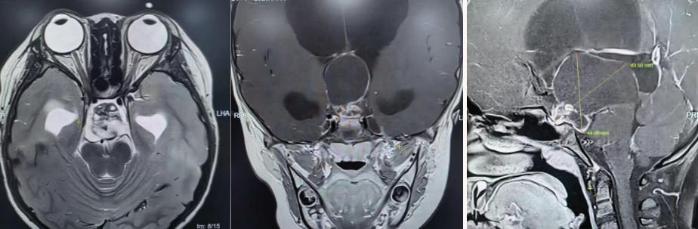

为精准掌握肿瘤情况,团队为欢欢完善了垂体MRI平扫+增强检查及相关激素水平检测。结果显示:肿瘤体积超过4厘米,形如鸡蛋,已严重压迫视神经与垂体,突入第三脑室,并与周围重要神经血管结构紧密粘连。

颅咽管瘤是一种起源于颅底的先天性良性肿瘤,因体积大、位置深,且毗邻下丘脑、视神经、垂体等重要结构,手术切除难度极高,稍有不慎就可能导致失明、终身内分泌紊乱甚至有生命危险。